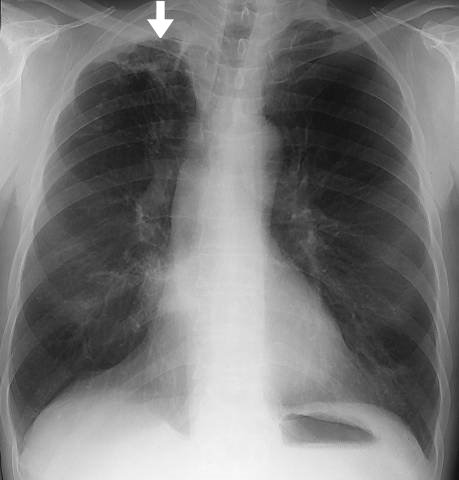

Tuberculous Reinfection in the Apex of the Right Lung

Tuberculous reinfection in the apex of the right lung. Tuberculous reinfection in the apex of the right lung. The image shows streaky opacities, tuberculous pneumonia and a thick-walled cavity (arrow).

Picture: Duodecim Medical Publications Ltd